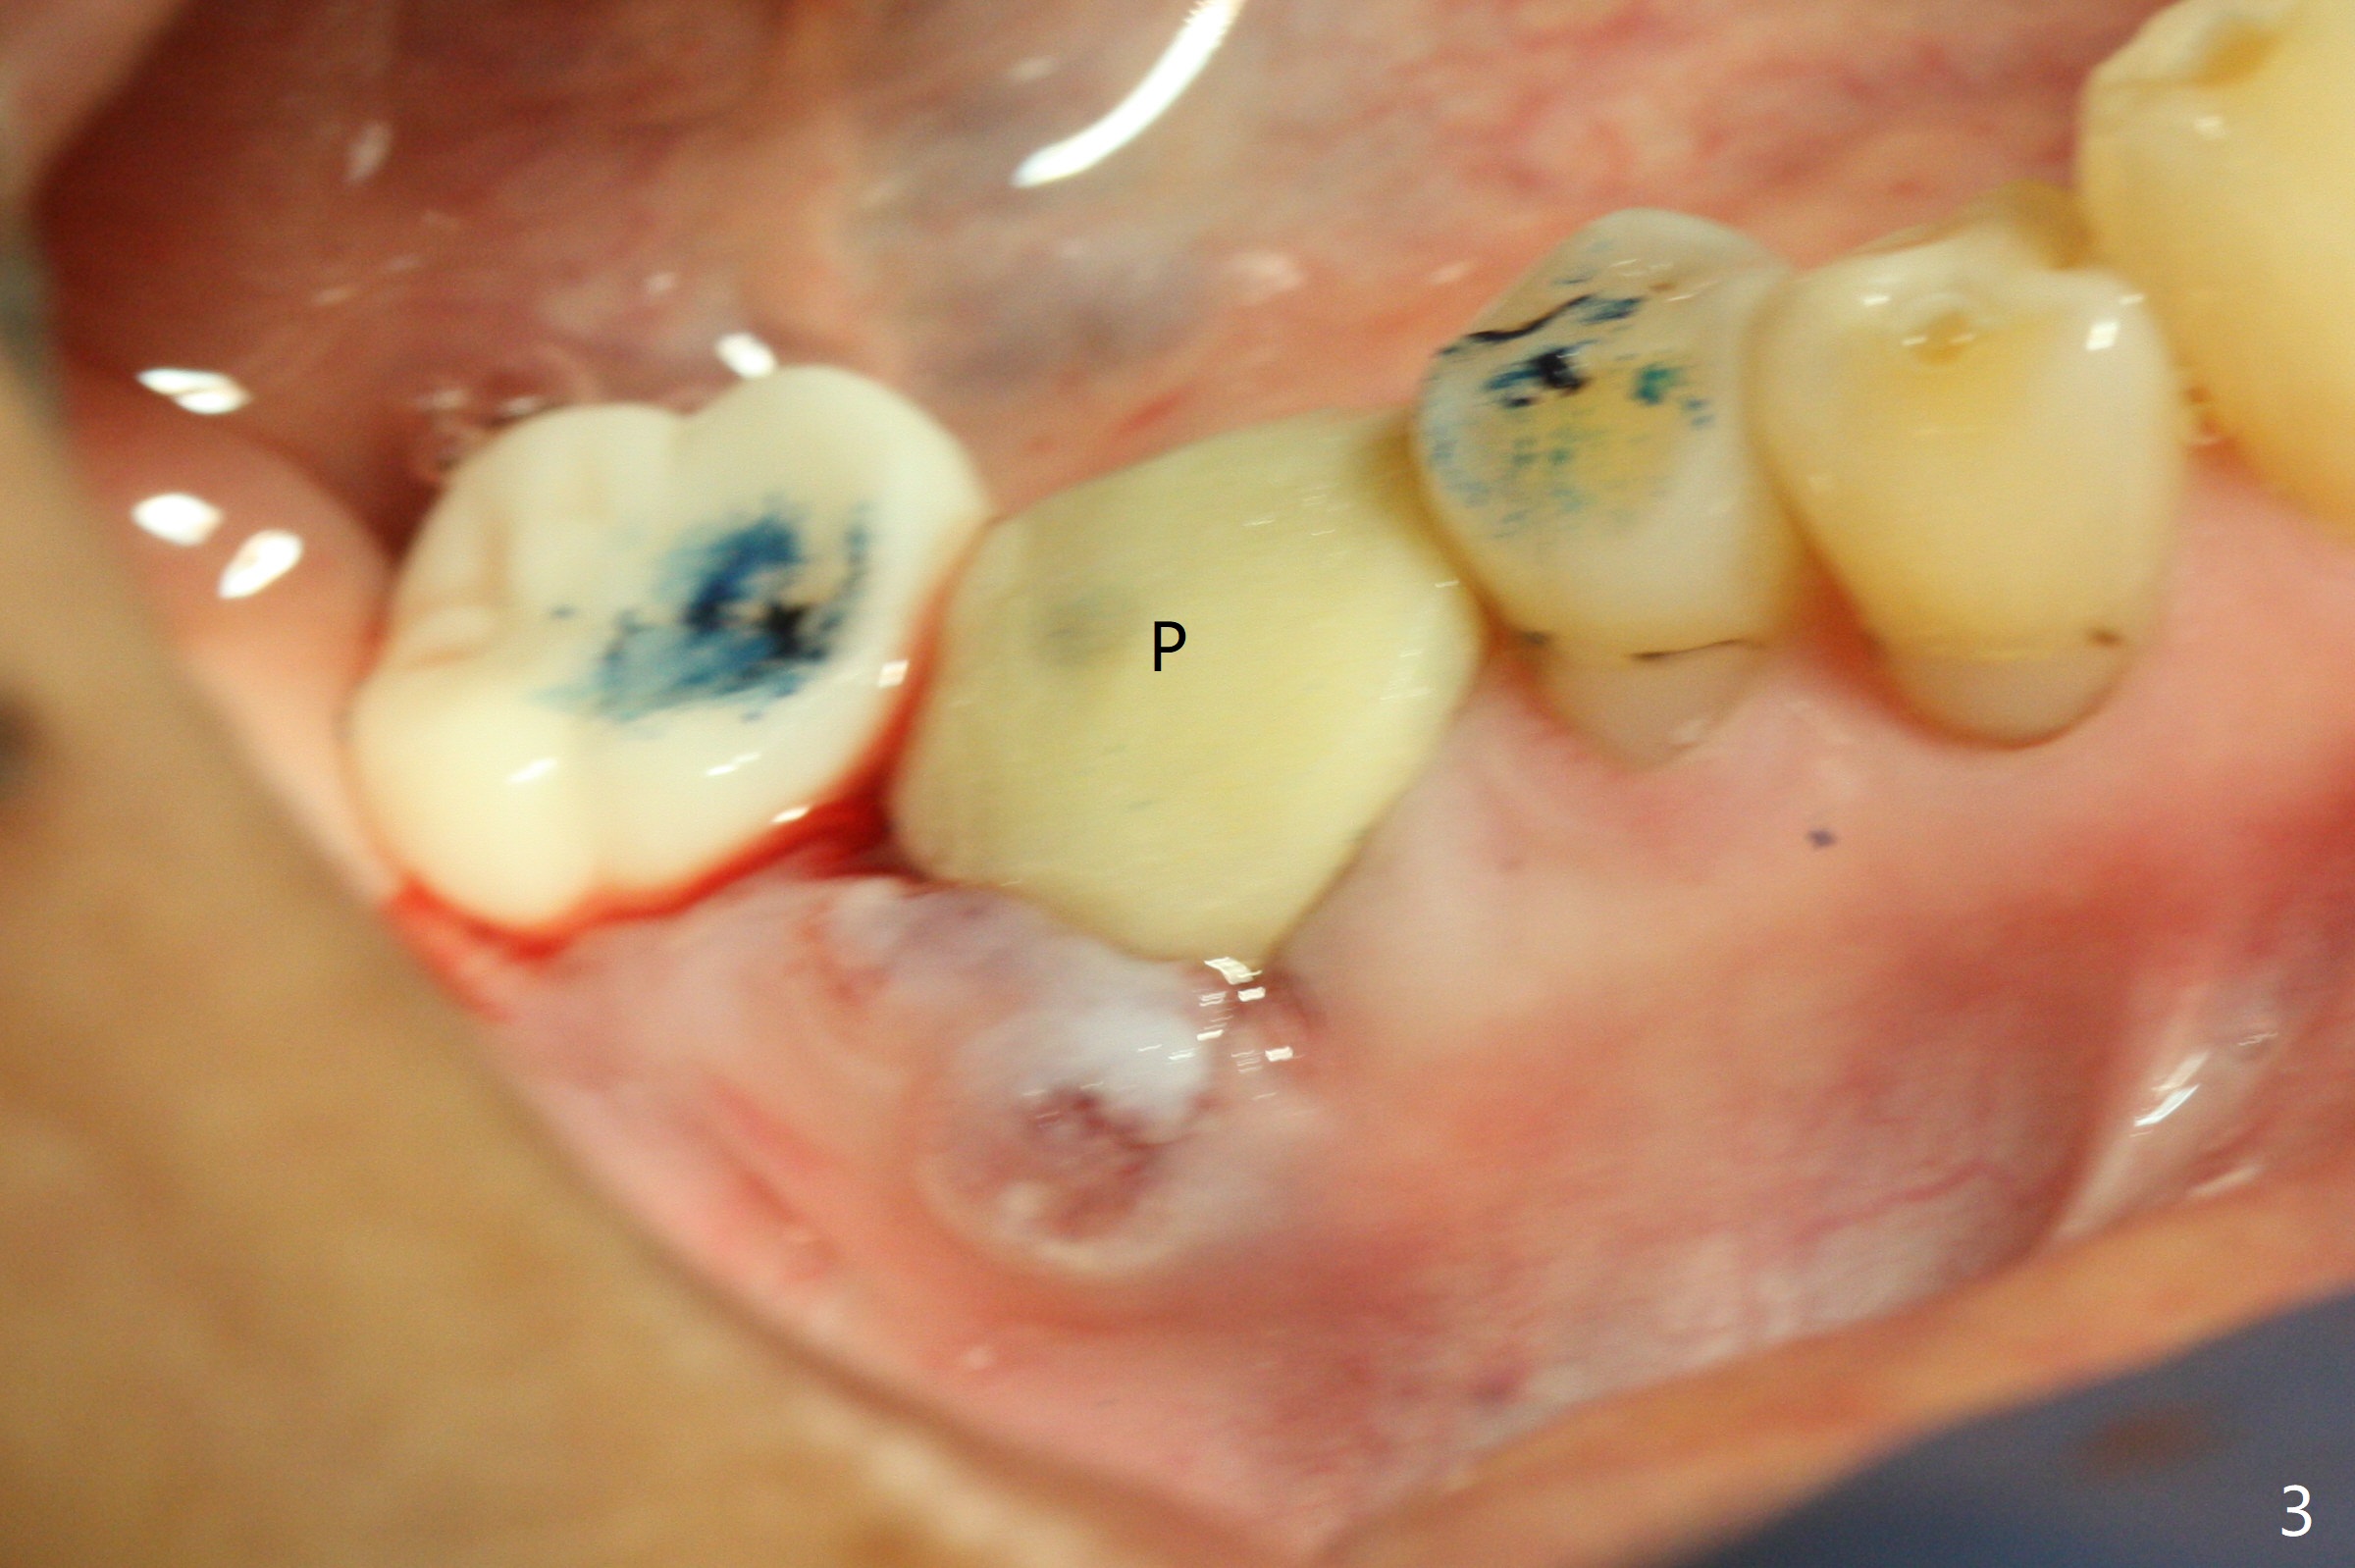

As compared to guided delayed implant placement, the immediate one in the 1st molar needs one more Lidocaine and one Septocaine for pain control. Trajectory is as good as expected with >50 Ncm (Fig.1,2 (red dashed line: superior border of the Inferior Alveolar Canal)). With insertion of Vanilla allograft with autogenous bone (Fig.1 *) and a 6.5x4(3) mm cementation abutment, an immediate provisional (Fig.3 P) is fabricated to keep the graft in place.